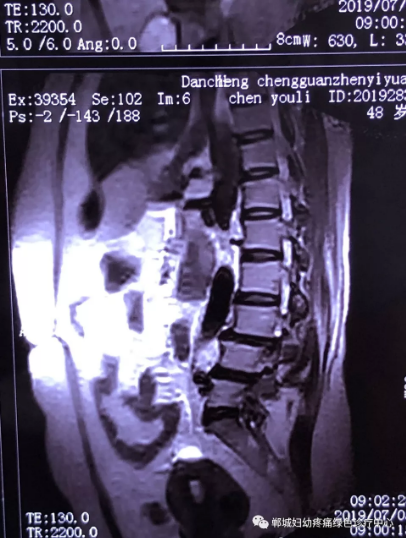

2年前,雙樓鄉(xiāng)的陳女士不小心摔了一跤后出現(xiàn)腰痛,當(dāng)時(shí)到藥店買了膏藥來貼,疼痛減輕了一些,但是從此以后反反復(fù)復(fù)出現(xiàn)腰痛。到處進(jìn)行治療,不見好轉(zhuǎn),最近腰痛加重了,痛得受不了,出現(xiàn)行走后甚至持續(xù)的雙下肢后側(cè)或后外側(cè)放射性的疼痛麻木、間歇性跛行等癥狀。陳女士趕忙去醫(yī)院治療,做了磁共振檢查后確診為腰椎滑脫、腰椎反弓。醫(yī)生都告訴她需要手術(shù)治療。隨后她又帶著片子咨詢了好幾家醫(yī)院,結(jié)果都是一樣,她已經(jīng)做好了手術(shù)的打算。

治療前

不經(jīng)意間聽到有人說醫(yī)院疼痛科可以不吃藥不打針,用無痛苦、無創(chuàng)傷的方法治療腰痛。陳女士就抱著試試看的心理來到了鄲城縣婦幼保健院疼痛科,疼痛科時(shí)慶祥主任詳細(xì)了解病情,結(jié)合腰椎磁共振及體征后告訴陳女士她不用手術(shù),通過腰椎脊柱定位周期減壓牽引系統(tǒng)(外星艙)也能解決腰痛、腰椎滑脫、腰椎反弓這些問題。陳女士未曾想到經(jīng)過十五天的治療后腰部及下肢放射性疼痛癥狀基本消失。陳女士感到十分激動與感謝,就在當(dāng)?shù)匦l(wèi)生院做了一個(gè)腰椎正側(cè)位x片和之前的片子作對比,發(fā)現(xiàn)腰椎滑脫明顯改善。她說道:感謝鄲城縣婦幼保健院疼痛科的所有醫(yī)護(hù)人員、感謝外星艙脊柱減壓治好了我的腰痛,也感謝告訴我來這里的人,她的一句話,讓我省了好幾萬元的手術(shù)費(fèi)!